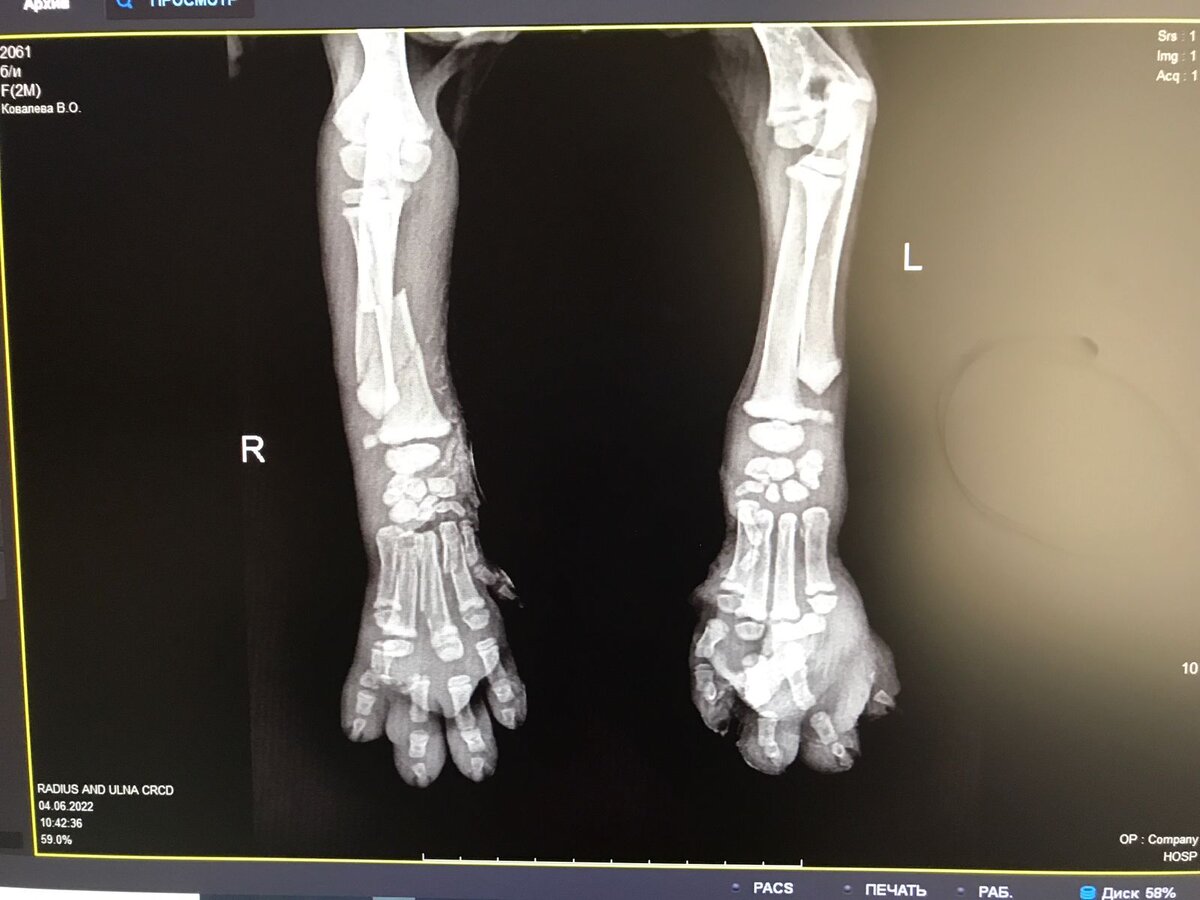

Астрахань. Мы снова с огромным поклоном к вам и вашим добрым сердцам наши дорогие помощники🙏Беда за бедой с малышами. Очередной малыш попал под колёса ,мы задыхаемся .   Перелом лапы, перелом пальчиков на обеих передних лапках с раздроблением. Малыш не ходит😢😢😢 ему очень очень больно и он не понимает что вдруг случилось.  Без операции он не встанет на ножки. На улице уже жара под сорок, мошки, комары он погибнет без помощи. Но мы же сможем ему помочь? Каждый из нас, по чуть-чуть, 50, 100 рублей,нам помогут спасти жизнь ребёнка🙏 Сумма к сбору 15000₽,сюда входит операция + лекарства ,питание,уход,на рентген собрали благодаря Вам, спасибо🙏💕 Отчёт гарантируем.  ✅💳СБ 4817760346095692 Козырева Фания ✅Corona pay +79880728361(для зарубежных переводов ✅СБП+79880728361 Ю maney 4100117820381855 ❗PayPal по запросу в личку. ✅💳Tинькофф 4377727814859026   Привязан к ☎+7 964 886-93-01 #лапка_перелом_астр #нужнафинпомощь #спаситежизнь

Перелом лапы, перелом пальчиков на обеих передних лапках с раздроблением. Малыш не ходит😢😢😢 ему очень очень больно и он не понимает что вдруг случилось.

Без операции он не встанет на ножки. На улице уже жара под сорок, мошки, комары он погибнет без помощи. Но мы же сможем ему помочь?